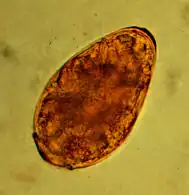

Die Infektion mit Hakenwürmern bleibt bei Katzen häufig symptomlos. Bei stärkerem Befall können sie Abmagerung, Blutarmut oder Durchfall auslösen. Der Nachweis der Infektion erfolgt wie bei Spulwürmern über den Nachweis der Eier im Kot mittels Flotationsverfahren. Sie sind oval, kleiner als Spulwurmeier (etwa 60×40 µm groß) und im Inneren sind bereits bei der Eiablage Furchungsstadien erkennbar.

Am häufigsten kommen Haarwürmer als Parasiten im Magen-Darm-Trakt bei Katzen vor, beispielsweise Capillaria putorii. Sie gelten als wenig krankheitsauslösend, rufen aber gelegentlich Erbrechen und Durchfall und selten auch Magengeschwüre mit Blutarmut hervor.[7] Die Eier von Magen-Darm-Haarwürmern sind oval, etwa 60–70 × 35–40 µm groß und lassen sich mittels Flotationsverfahren nachweisen.[8]

Die Infektion mit dem Nierenwurm (Dioctophyme renale) ist nur in Südeuropa, Asien und Nordamerika anzutreffen und auch dort bei Katzen selten, der Hauptwirt sind Nerze. Der Nierenwurm ist mit bis zu einem Meter Länge der größte parasitisch lebende Fadenwurm und zeigt einen zweifachen Wirtswechsel: Erster Zwischenwirt sind Wenigborster, zweiter Süßwasserfische. Er parasitiert im Endwirt vor allem im Nierenbecken oder -fett. Der Befall einer Niere verläuft meist ohne Krankheitszeichen. Sind beide Nieren betroffen, können Nierenfunktionsstörungen infolge einer Hydronephrose oder Pyelonephritis auftreten. Die Infektion lässt sich durch eine Nierenbiopsie oder bildgebende Verfahren nachweisen. Die fassförmigen, gelbbraunen und 71–84 × 45–52 µm² großen Eier treten nur im Urinsediment auf, wenn ein weiblicher und männlicher Nierenwurm in einer Niere aufeinandertreffen.[10]

Im selben Tier sind zumeist nur zwei bis zehn Katzenbandwürmer anzutreffen, täglich scheiden sie etwa vier bis fünf Glieder aus. Diese länglich-trapezförmigen Gebilde sind unter Umständen bereits in der Analregion mit bloßem Auge sichtbar. Die etwa 35 µm großen beschalten Onkosphären lassen sich mittels Flotationsverfahren im Kot nachweisen. In einer Studie konnte bei Obduktionen eine Befallsrate von 25,9 % ermittelt werden, von denen nur 10 % im Flotationsverfahren beziehungsweise 27 % nach Zentrifugation erkannt wurden.[15] Zudem können die Eier morphologisch nicht von denen anderer Vertreter der Taeniidae (einschließlich des Fuchsbandwurms) unterschieden werden.

Der Befall mit dem Gurkenkernbandwurm lässt sich durch den Nachweis der Glieder in der Analregion oder den Nachweis der 35–53 µm großen Eier oder von Eipaketen im Kot mittels Flotationsverfahren feststellen. Allerdings sind diese Nachweisverfahren sehr unsicher. In einer Studie konnte bei Obduktionen eine Befallsrate von 34,5 % ermittelt werden, obwohl alle vorherigen Kotuntersuchungen negativ ausfielen.[15]